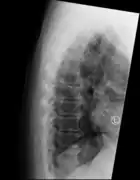

"Melted candle wax" appearance of calcification and ossification in diffuse idiopathic skeletal hyperostosis (DISH). Note the preponderance on the patient's left side (right side of image).

The calcification and ossification is most common on the right side of the spine. In people with dextrocardia and situs inversus this calcification occurs on the left side.[10]